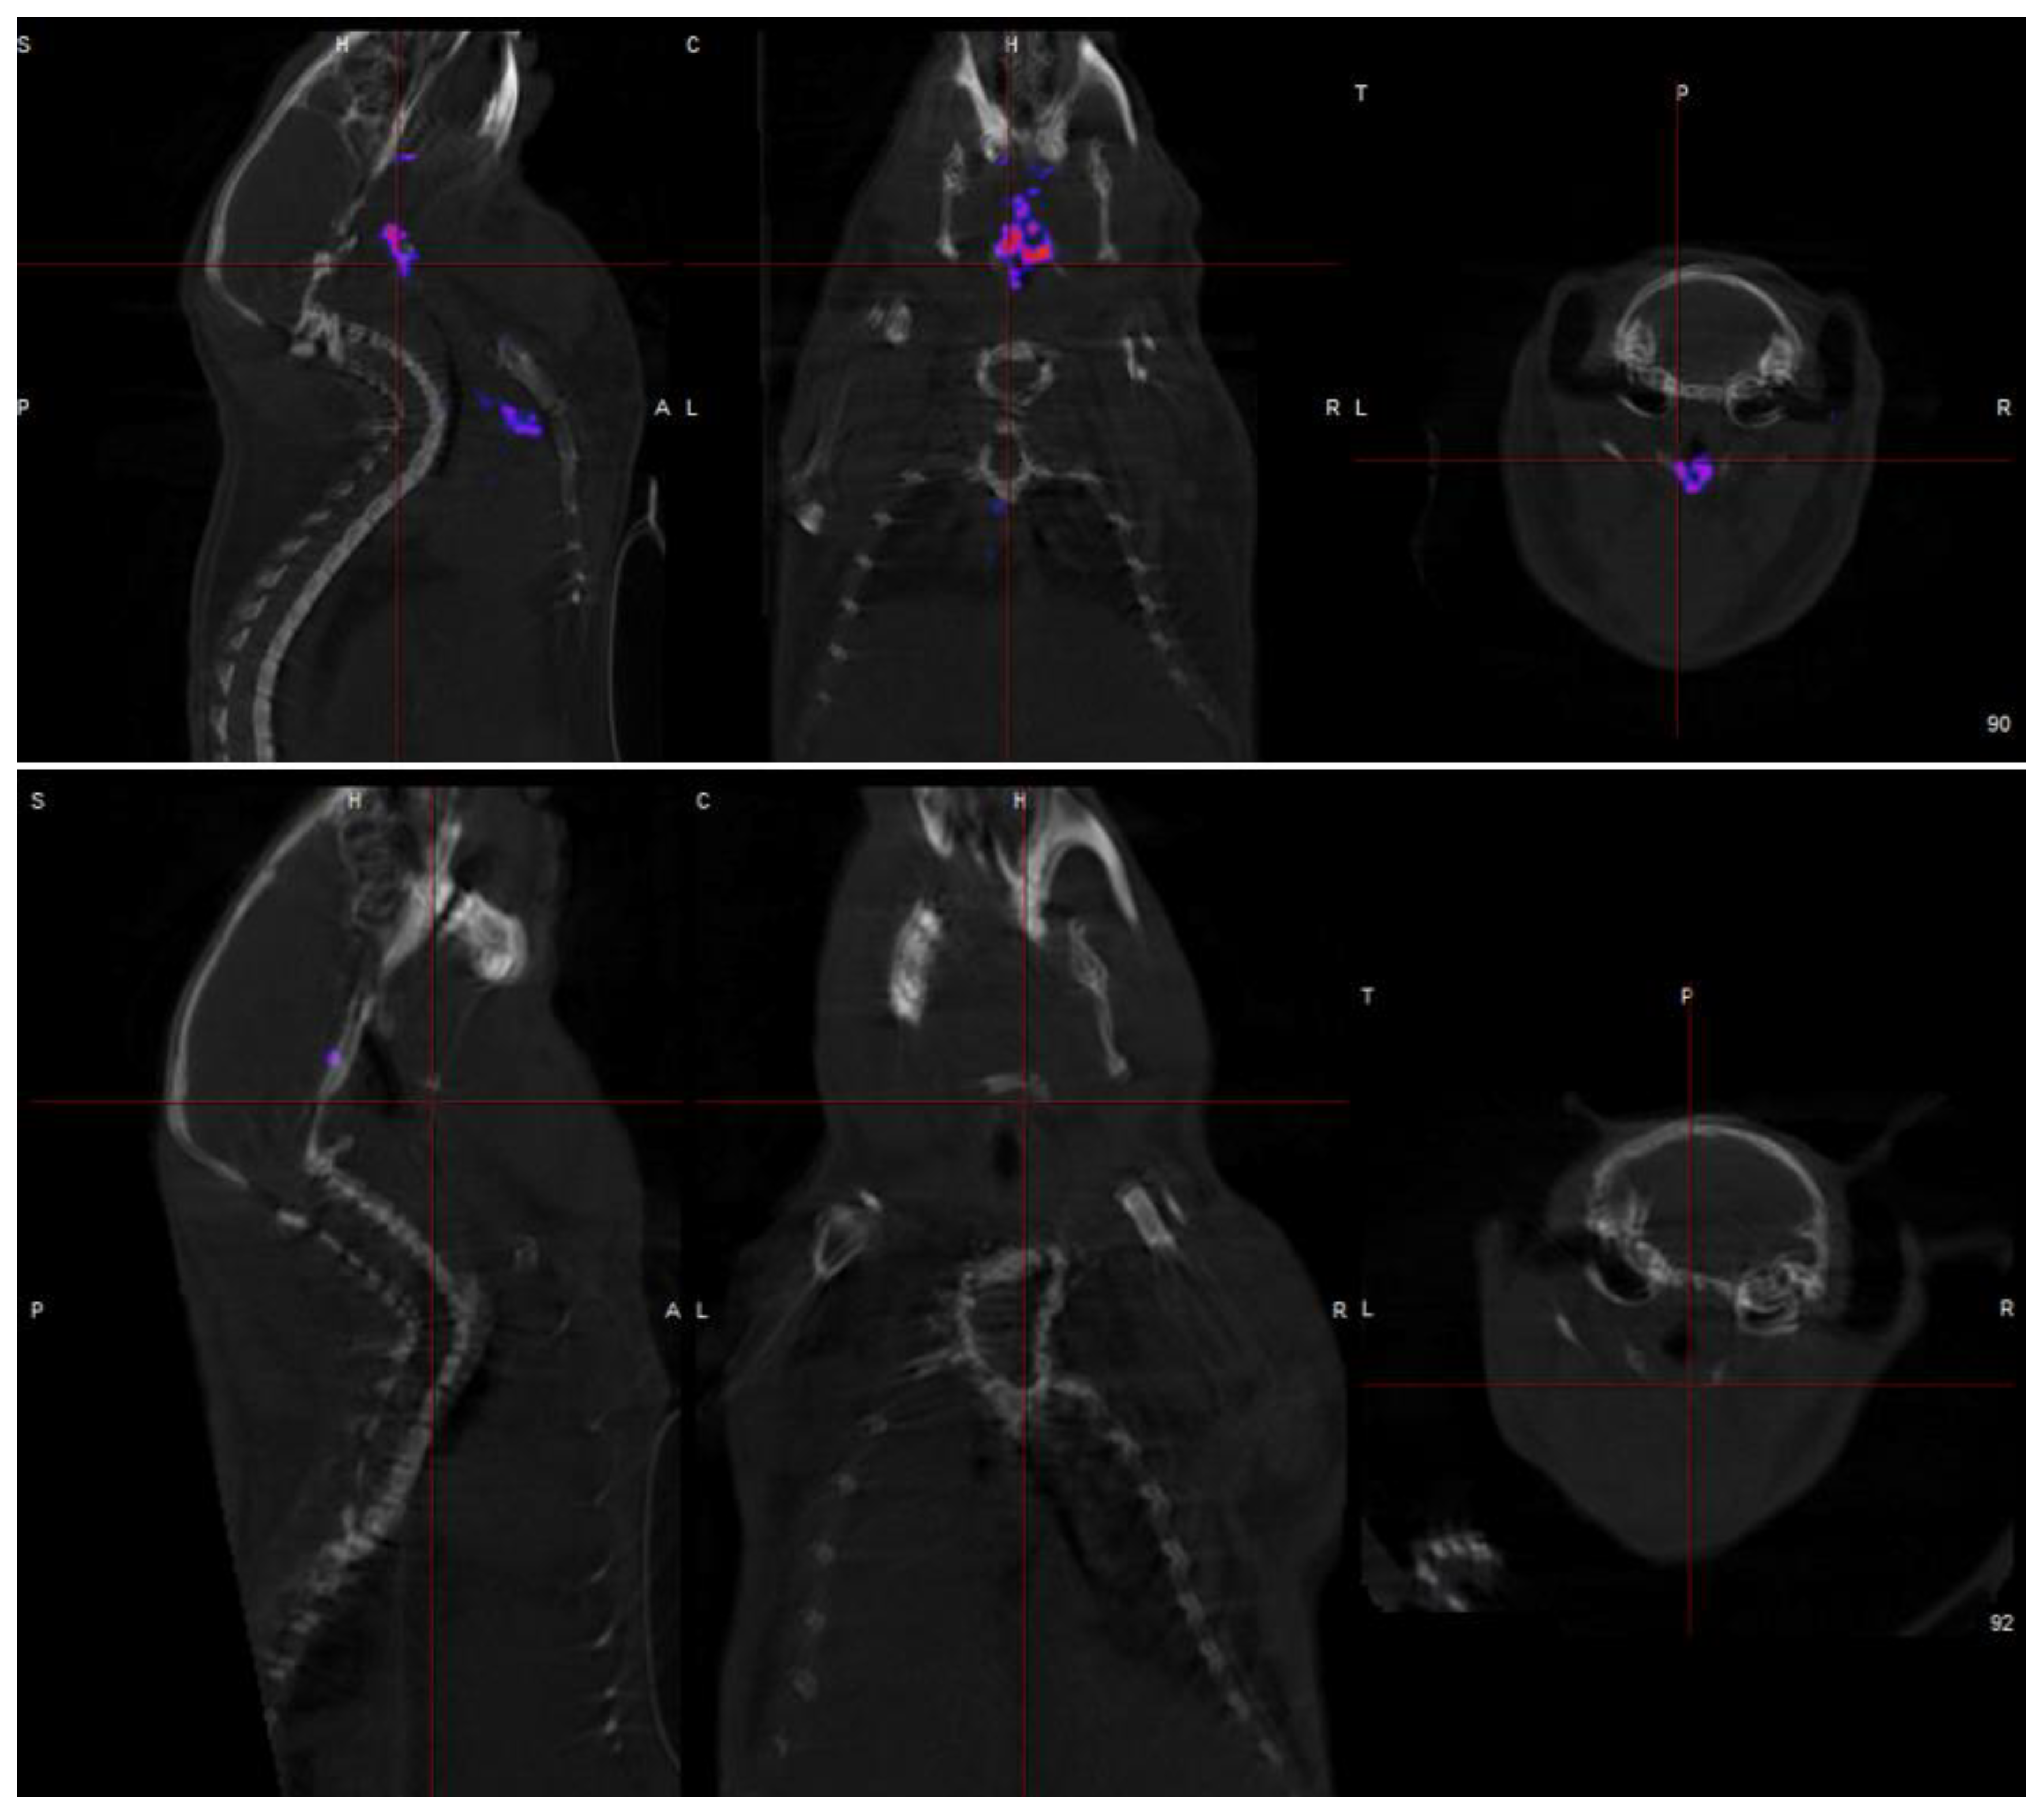

- Dweck, M.R.; Chow, M.W.; Joshi, N.V.; Williams, M.C.; Jones, C.; Fletcher, A.M.; Richardson, H.; White, A.; McKillop, G.; van Beek, E.J.; et al. Coronary arterial 18F-sodium fluoride uptake: A novel marker of plaque biology. J. Am. Coll. Cardiol. 2012, 59, 1539–1548. [Google Scholar] [CrossRef]

- Joshi, N.V.; Vesey, A.T.; Williams, M.C.; Shah, A.S.V.; A Calvert, P.; Craighead, F.H.M.; Yeoh, S.E.; Wallace, W.; Salter, D.; Fletcher, A.M.; et al. 18F-fluoride positron emission tomography for identification of ruptured and high-risk coronary atherosclerotic plaques: A prospective clinical trial. Lancet 2014, 383, 705–713. [Google Scholar] [CrossRef]

- Early detection of vulnerable coronary plaques because 18F NaF accumulation in micro-calcification before visibility on CT, allowing earlier intervention. Furthermore, 18F NaF uptake can differentiate between active and indolent calcification in coronary arteries, providing crucial information on plaque activity and potential instability.